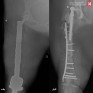

بعد 5 محاولات جراحية لم تنجح.. مستشفى الحبيب بالخبر يُمكّن سبعينية من المشي مجددًا

الواحة نيوز

10:28 ص - 10 نوفمبر، 2025